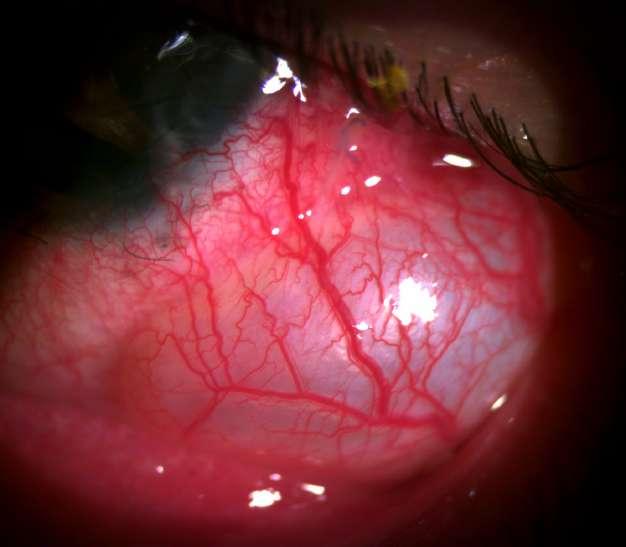

4.C. ROSÁCEA OCULAR

ü Hombre 67 años consulta por cuadro de 2 años de evolución de dolor ocular y disminución de la agudeza visual. Refiere estar usando desde hace 1 año Loteprednol tópico.

ü Hiperemia e inyección conjuntival

ü Neovascularización estromal

ü Telangectasias

ü Pannus en 360º

ü Opacidad corneal + neovasos estromales